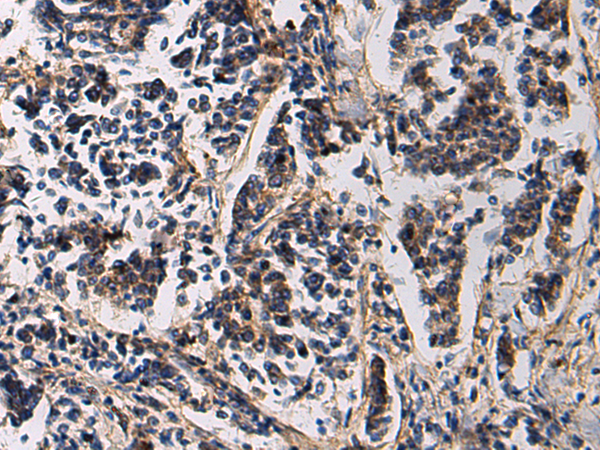

IHC positive control: |

Human esophagus cancer and Human breast cancer |

IHC Recommend dilution: |

50-200 |